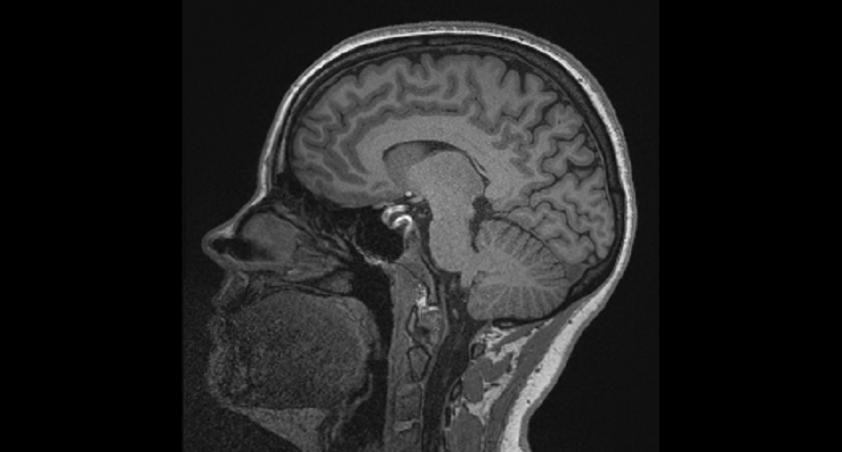

The new research MRI will enable scientists at the Bloorview Research Institute and externally to examine the human condition in children, youth and adults with and without disabilities.

This MRI technology will allow scientists to scan thousands of children and adolescents as well as adults living with and without disabilities in ground-breaking research studies on a large scale.